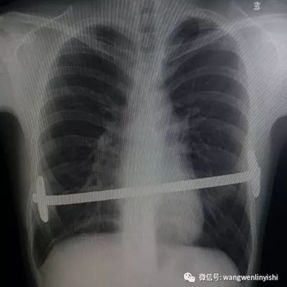

The patient’s anterior chest wall exhibits a prominent depression deformity,characterized by a horizontal groove that affects both sides of the anterior chest wall. There is a surgical scar along the midline and one on the left side, with two scars visible on the right side of the chest wall. A 4x4 cm mass is located on the left chest wall, characterized by darkened skin and noticeable fluctuation upon palpation. The mass extends deep into the intercostal space. Mild scoliosis is also observed. The patient was ultimately diagnosed with grooved chest.

2. Improper bar Placement and Positioning: Preoperative imaging reveals that the bar was positioned along the upper edge of the groove-like depression and was placed at an angle.For optimal support and effective correction of the depressed bony structure, the bar should have been positioned at the base of the depression.

3. Insufficient Number of Bars: In adult patients, the larger chest wall depression and increased bone density generally necessitate the use of at least two bars during corrective surgeries to ensure adequate support and achieve the desired outcome. However, only one bar was used in the patient’s initial surgery, which was insufficient to effectively correct the depression.